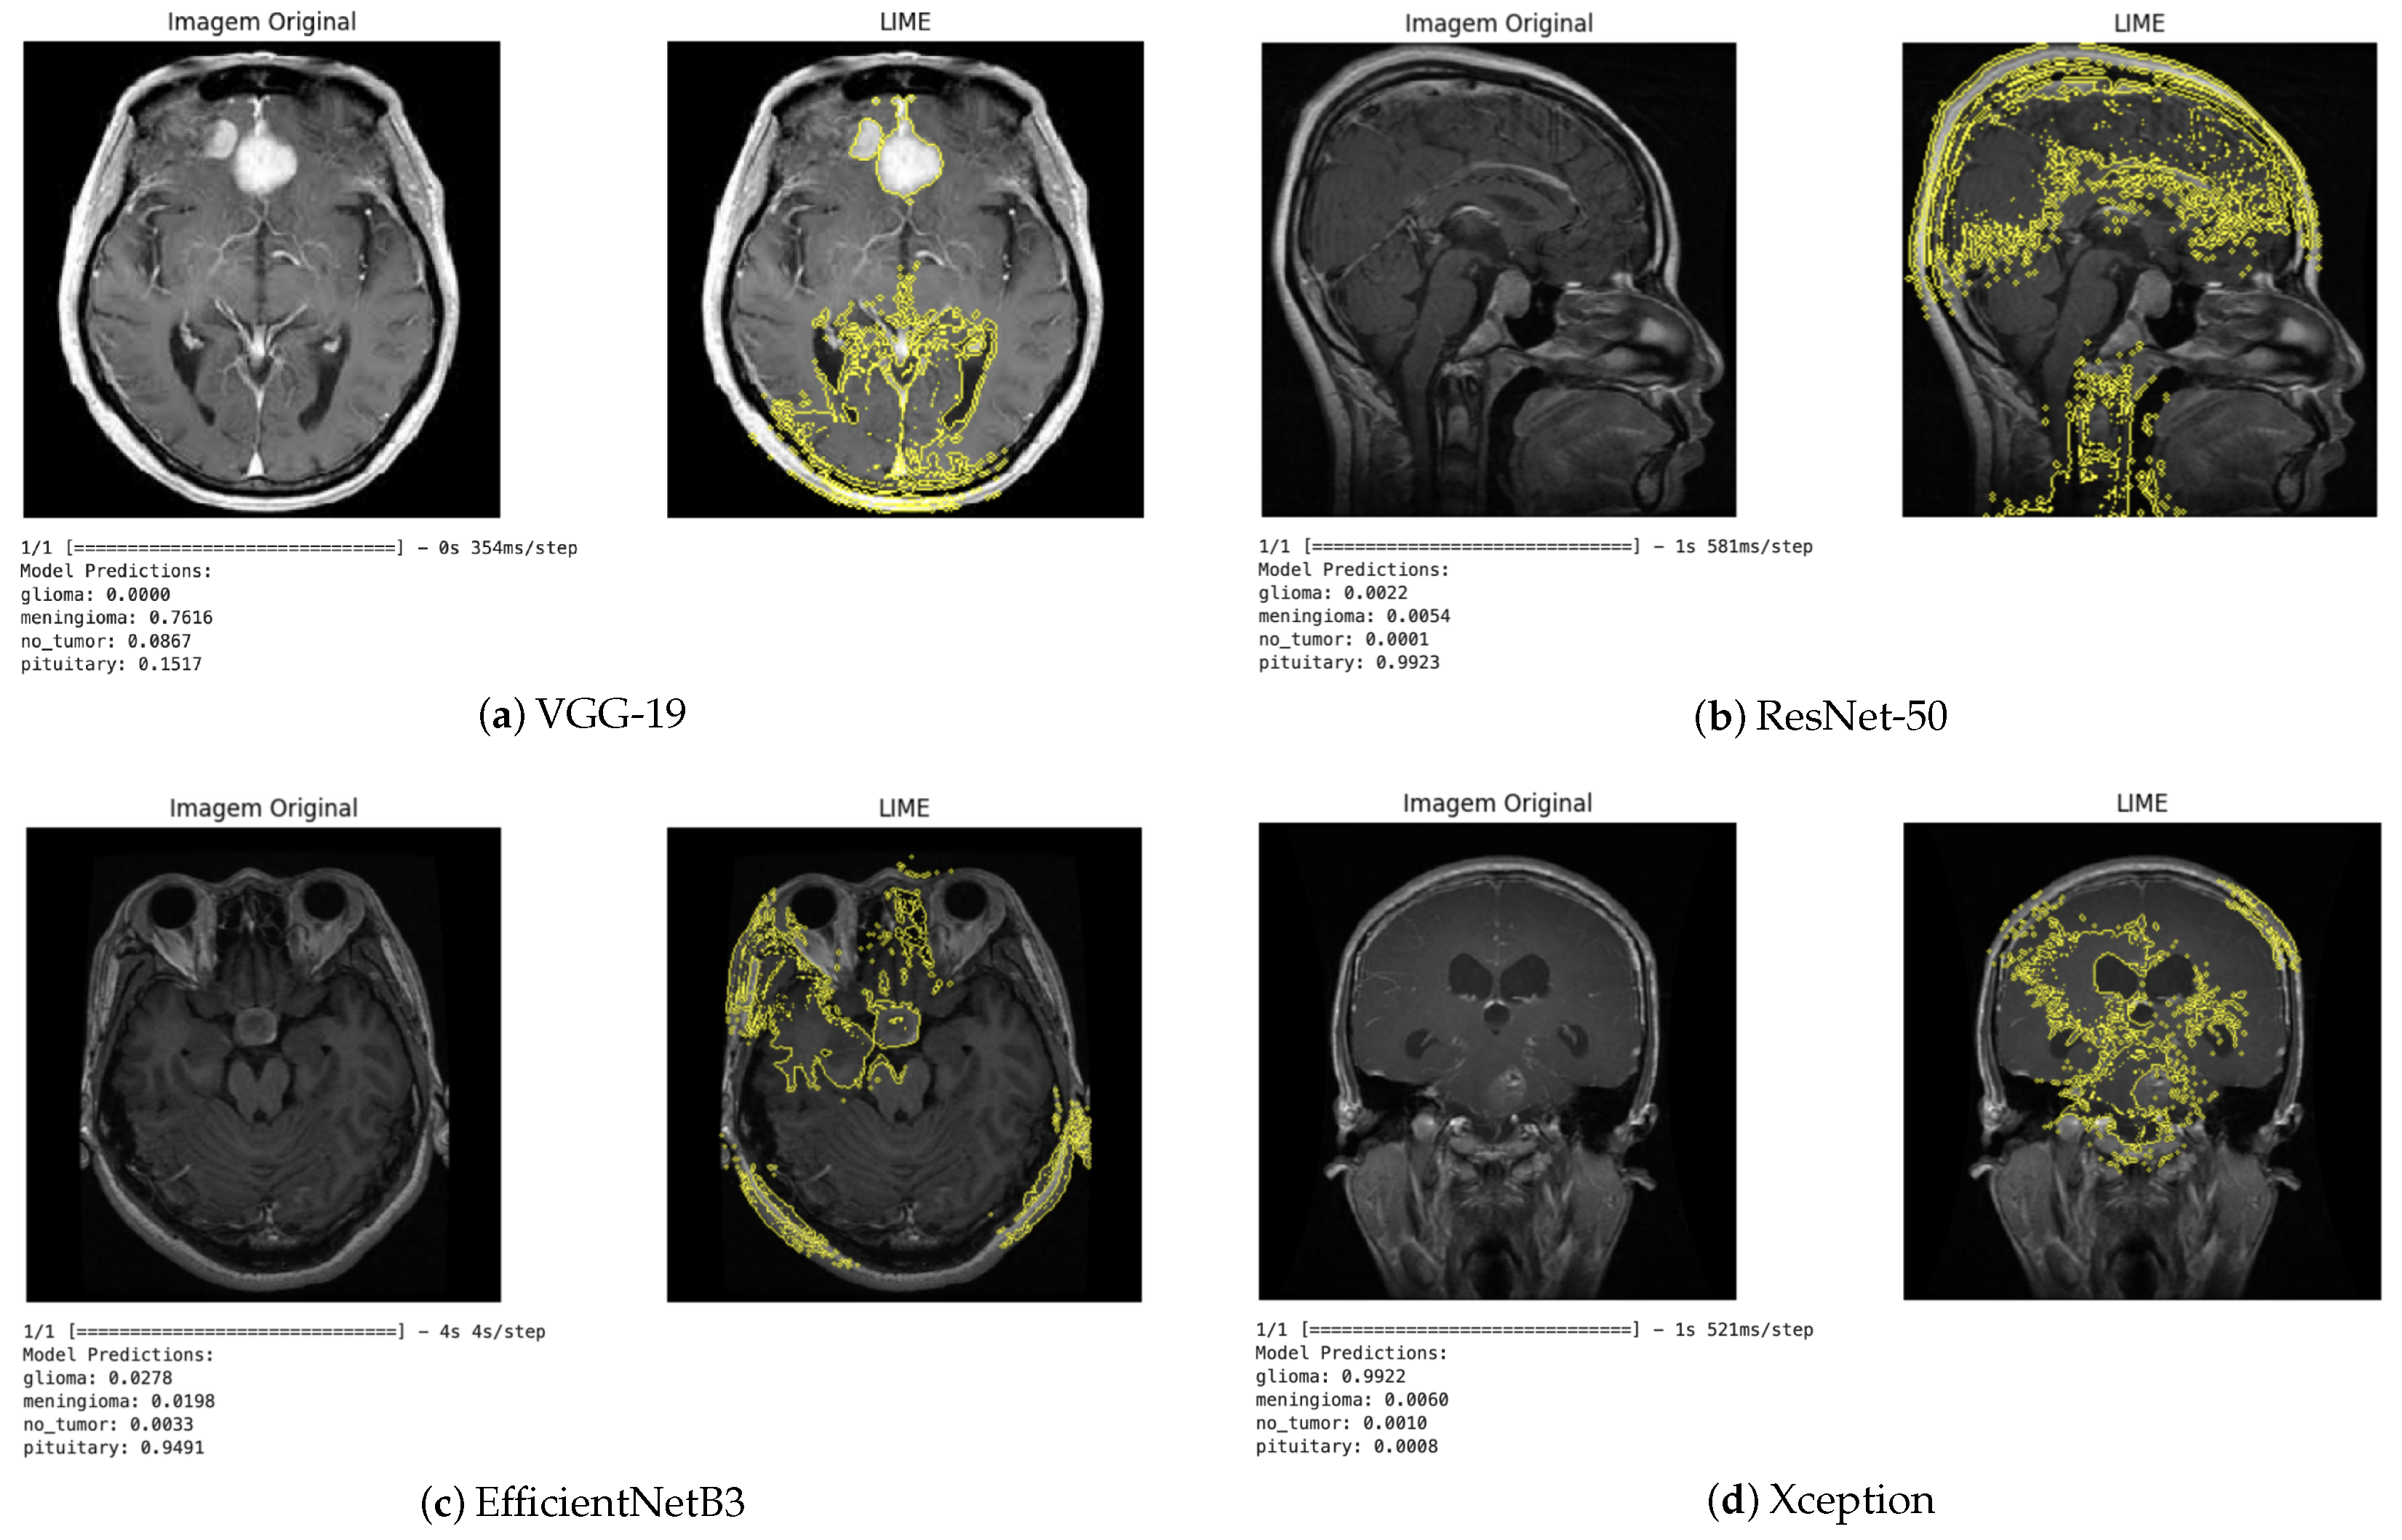

The LIME technique, in turn, provides local explanations by identifying which regions of the image contributed positively or negatively to the classification (Figure 10). This approach enabled a more detailed analysis of the influence of each image segment on the decision-making process. In general, the regions highlighted by LIME showed a high correspondence with those identified by Grad-CAM, reinforcing the consistency of the explanations produced by the different methods.

Figure 10.

LIME visualization for different architectures.